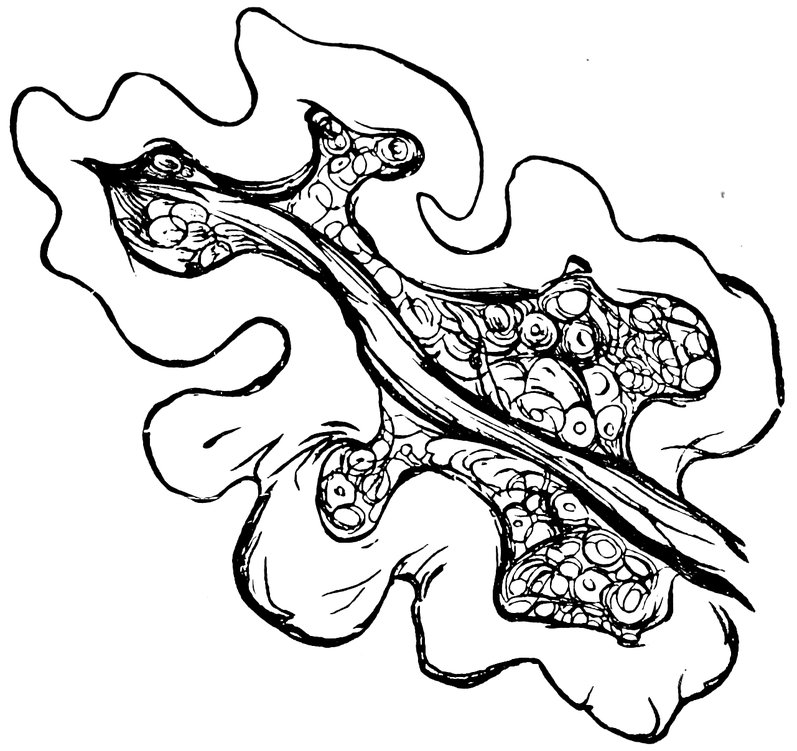

12The greater number of the spinal nerves distributed to the genital organs arise from the lumbar portion of the spinal cord, pass as rami communicantes to the first four lumbar ganglia of the great sympathetic cord, whence they proceed to the series of symmetrical (paired) and asymmetrical (azygos) sympathetic plexuses in front of, and adjacent to the abdominal aorta, which already contain afferent and efferent spinal fibres derived from the pneumogastric, phrenic, and splanchnic nerves. A small number only of coarse nerve-filaments, a larger number of fine nerve-filaments, derived from the sacral nerves, proceed direct to the internal genital organs; many of these fibres enter the lower extremity of the pelvic or inferior hypogastric pleans, some pass to the cervical ganglia of the uterus. Below the bifurcation of the aorta and in front of the sacral promontory, a large number of the uterine nerves, both of spinal and of sympathetic origin, unite to form an azygos plexus which has been shown by experiment to possess great functional importance. Anatomically this constitutes the upper undivided portion of the hypogastric plexus, which is the downward continuation of the abdominal aortic sympathetic plexus; but inasmuch as it is the principal channel of nervous impulses to the uterus it is often known at the present day as the great uterine plexus (plexus uterinus magnus). The nerves to the ovary and Fallopian tube (ovarian nerves) are derived from the spermatic (ovarian) plexus, an offshoot of the renal plexus; as the spermatic plexus descends, it is reinforced by branches from the abdominal aortic plexus, these branches often arising from a small ganglion (spermatic ganglion). The hypogastric or great uterine plexus, single and median above, divides below into the paired pelvic or inferior hypogastric plexuses, which pass downward and forward on either side of the rectum; these plexuses are reinforced by spinal elements derived from the sacral nerves. Before the terminal expansions of the pelvic or inferior hypogastric plexus enter the tissues of the internal genital organs, the bladder, and the rectum, small masses of ganglionic matter are interspersed among the nerve fibres.

To the above general sketch, which has been based on the synoptical description of Chrobak von Rosthorn, must be added a more detailed account of the innervation of the ovaries, this branch of the subject being of especial importance. The nerves of the ovary are derived from the sympathetic system, in part from the spermatic ganglion, in part from the second renal ganglion, and in part from the superior mesenteric plexus. The nerves of 13the ovary are for the most part vascular nerves, which unite before entering the ovary to form the ovarian plexus, and then pass into the hilum with the vessels, envelop the vessels of the medullary layer, and thence pass to the follicular region; exceedingly numerous, they form a close-meshed network, surrounding all the vessels up to the finest capillary ramifications; those fibres which terminate in the capillary walls and those also which reach the follicles are regarded by Riese as sensory. The great trunks of the uterine nerves are transversely disposed in relation to the great lateral vessels of the uterus, and passing inward toward the mucous membrane they break up into pencils of filaments; the uterine nerves proper are distributed for the most part to the muscular substance. In the Fallopian tubes, the nerves form arches around the lumen of the tube; some fibres also pass to the longitudinal folds of the mucous membrane.

This expansion of the nerves of the cerebrospinal and sympathetic systems in the female reproductive organs manifests the multiple interconnection of the two systems in this region, and proves beyond doubt that the sensory nerves of the genital organs have manifold connections with the motor tracts of the whole organism on the one hand and with the sensory ganglia of the central nervous system on the other, and in addition with the vasomotor centres and with efferent motor and secretory fibres.